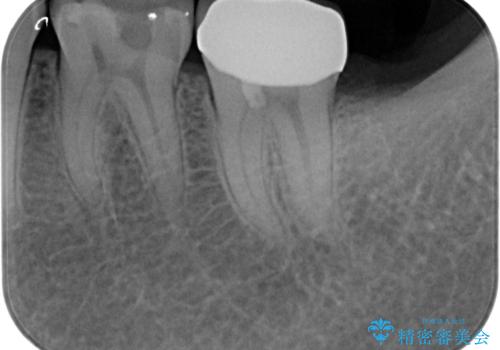

- 奥歯がしみるとのことで来院されました。

検査の結果、古い詰め物の裏側に虫歯ができていること(二次う蝕)が確認されたため、治療していくこととなりました。

- 左下7 生活歯髄療法:33,000円 仮歯+ジルコニアクラウン:11,000円+121,000円費用は治療当時の料金となります

虫歯が大きくても、今回のように神経を温存することができる場合があります。